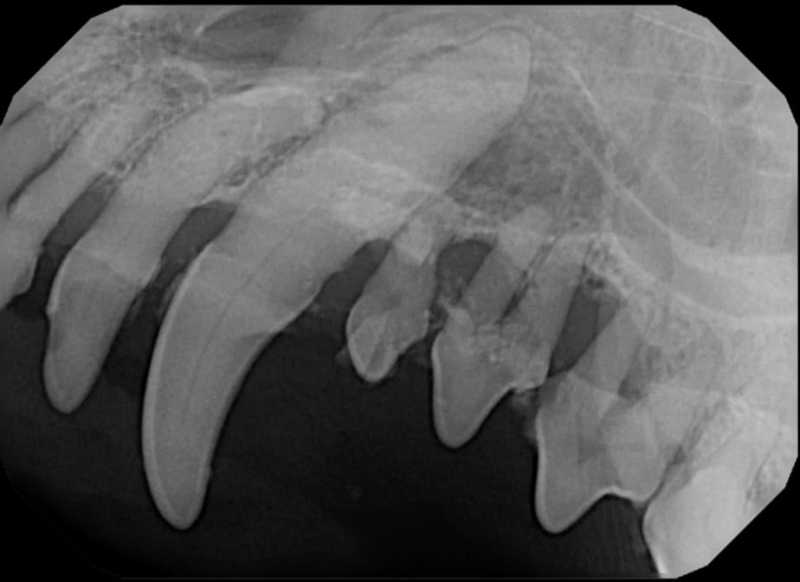

Tooth Resorption

Tooth resorption is a disease process where the body begins to break down the adult tooth. It is widely known to occur in cats but can also occur in dogs. In cats these lesions are thought to be inflammatory, while in dogs they can be more of a replacement resorption process. These lesions can be very painful and should be treated, generally with extraction depending on the type of resorption that is occurring. The disease can be progressive and affect many teeth over several years. It is important to have regular checkups and yearly dental cleanings to monitor for these lesions.